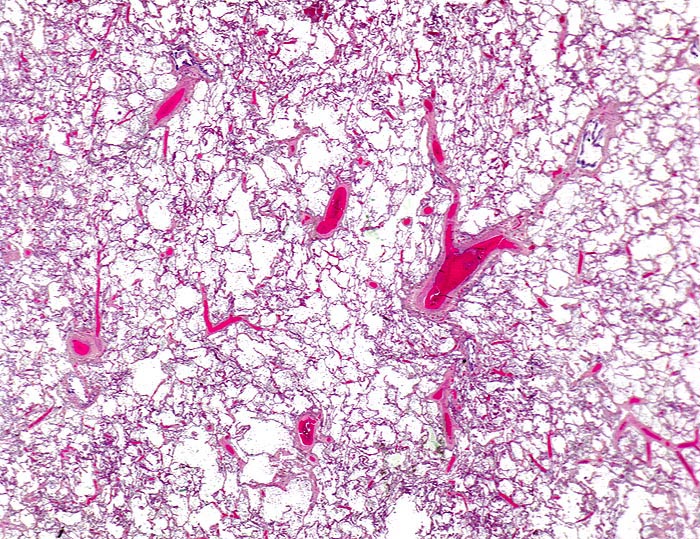

In einer frühen Phase kommt es zur roten Stauungsinduration, welche in eine braune Stauungsinduration übergeht. Die Eindrückbarkeit der Lungen ist aufgrund der Fibrosierung der Alveolarsepten vermindert. Die meist fleckförmige braune Verfärbung beruht auf der Anhäufung von hämosiderinhaltigen Herzfehlerzellen in den Alveolarlichtungen. Makrophagen in den Alveolarlichtungen phagozytieren die ausgetretenen Erythrozyten. Der Nachweis von Erythrozyten im Zytoplasma von Makrophagen spricht für eine frische Blutung. Nach 3-5 Tagen ist in den Makrophagen Hämosiderin nachweisbar. Das Hämosiderin lässt sich mittels Eisenfärbung (Berliner-Blau) zuverlässig von Staubpigment abgrenzen. Als sicheres Zeichen für eine ältere Blutung gelten >20% hämosiderinspeichernde Makrophagen in der bronchoalveolären Lavage (BAL). Die hämosiderinhaltigen Alveolarmakrophagen werden auch Herzfehlerzellen genannt, da sie gehäuft im Rahmen einer linkskardialen Stauung bei Mitralklappenstenose auftreten.

Aufgrund des erhöhten Druckes in den Lungenkapillaren kommt es zur sekundären Pulmonalarteriensklerose. Die Befunde an den Pulmonalarterien sind bei primärer und sekundärer pulmonaler Hypertonie prinzipiell gleich. Die Pulmonalarterienhauptstämme zeigen Atherombildungen (> 3698) (> 3589) und eine Mediafibrose. Die elastischen Pulmonalarterienäste entwickeln atheromatöse Polster, welche makroskopisch als gelbe Flecken erkennbar sind. Ulzera oder Verkalkungen wie in den Arterien des grossen Kreislaufes werden jedoch kaum beobachtet. Die Veränderungen an kleineren muskulären Arterien (Mediahypertrophie, zelluläre Intimaproliferation, Intimafibrose, Wandnekrosen bei sehr hohen Drücken) und Venolen (Venulosklerose) sind nur histologisch nachweisbar.

• Mediahypertrophie der Pulmonalvenen.

• Fibrosierung und Verdickung der Alveolarsepten.

• Siderinhaltige Alveolarmakrophagen (=Herzfehlerzellen).